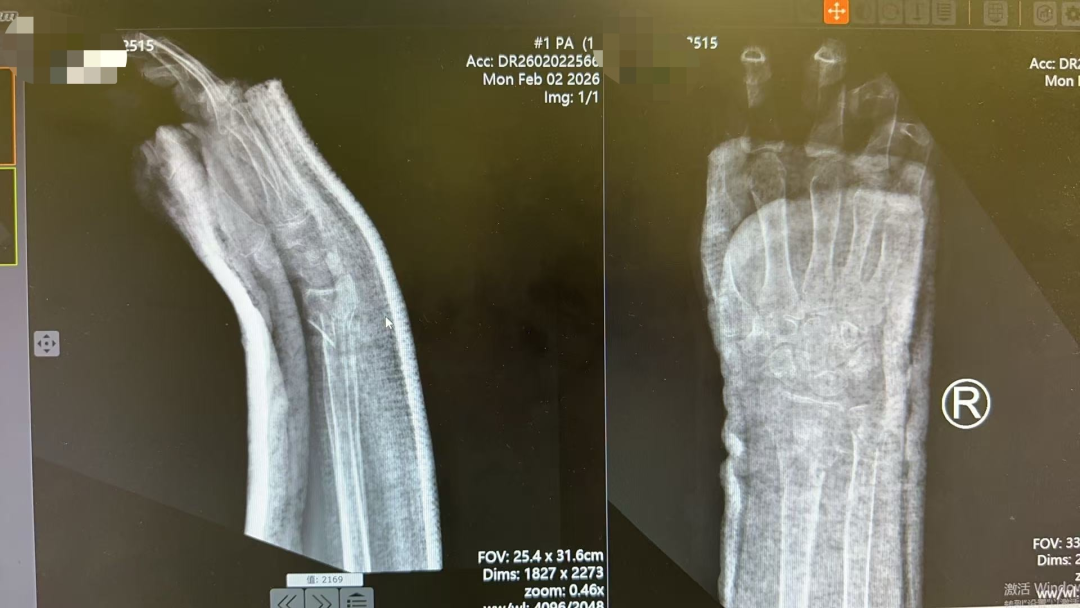

接诊后,薛安邦主治医师详细询问病史、认真查体,并结合影像学资料,明确诊断为右尺桡骨远端粉碎性骨折伴移位。影像显示,骨折端严重粉碎、移位显著,且累及关节面,属高难度、高风险类型,治疗难度极大。更为棘手的是,患者年逾八旬,身体机能衰退,合并多种基础疾病,若选择手术治疗,麻醉及围术期风险极高。因此,保守治疗成为更优选择,但对复位技术提出了更高要求。

方案确定后,在董博主任的指导下,薛安邦与周健副主任医师默契协作,凭借精湛娴熟的手法技艺和丰富的临床经验,轻柔稳健地将移位的骨折碎片逐一精准复位。整个过程流畅有序,力道把控恰到好处。复位后复查X线显示,骨折端达到功能对位。董博主任表示,考虑到患者高龄不耐受强刺激,先以功能复位为核心,后期可通过加垫调整逐步优化复位效果。